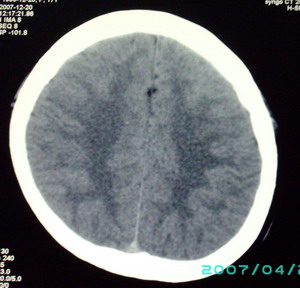

以下是引用九目段在2007-12-24 14:55:00的发言:[br]1,年轻女性[br]2,ct表现:左侧脑室三角区可见一不规则小明显强化的结节,中央见小低密度,侧脑室无扩张。[br]分析:[br]常见的有三种肿瘤好发三角区:[br]1,脉络丛乳头状瘤,好发于年轻者,明显强化,实性,分泌脑脊液,常伴有侧脑室扩大,肿瘤较小可以脑室扩大不明显,不能排除,但小结节尚不易形成坏死腔。[br]2,室管膜瘤,好发于儿童及青少年,明显强化,易坏死,大时伴脑室扩张。[br]3,脑膜瘤,明显强化,圆形,界请,无脑积水,一般不坏死。[br]诊断:[br]左侧脑室三角区结节,考虑室管膜瘤可能性大,不排除脉络丛乳头状瘤和脑膜瘤(因病史较长)。[br][br][本贴已被 九目段 于 2007-12-24 15:13:35 修改过]